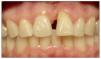

Figura 7. Paciente rehabilitado.

Figura 12. Imagen a los 6 meses con provisorio adhesivo.

Figura 14.Paciente rehabilitado.